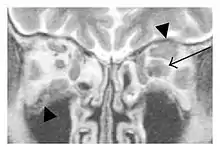

The extent of inflammation that can occur in IgG4-ROD is well demonstrated on magnetic resonance imaging (MRI).

![]() Swelling of the left superior and lateral rectus muscles, a mass lesion around the left optic disc (arrow), and enlargements of the left supraorbital nerve and the right infraorbital nerve (arrow heads) in a 60-year-old man with a serum IgG4 of 463 mg/dL.[1] (T1-weighted MRI) |